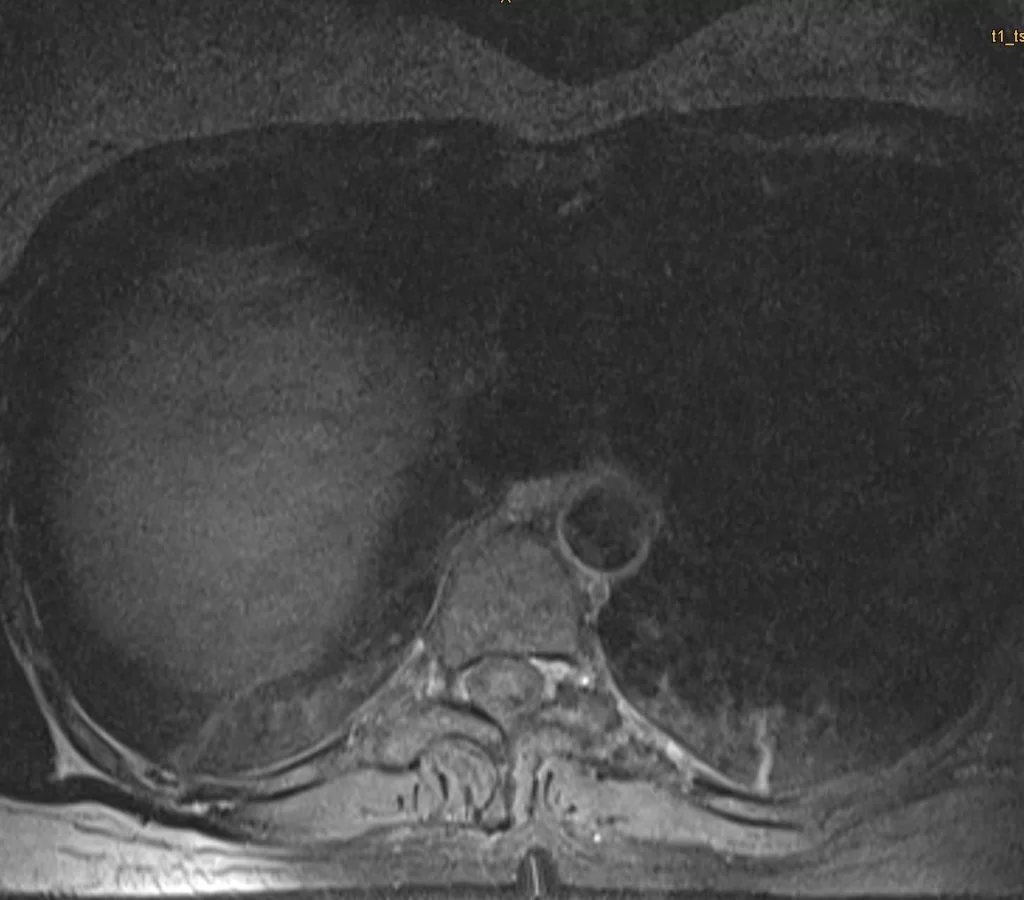

Ο απεικονιστικός έλεγχος με μαγνητική τομογραφία ανέδειξε ευμεγέθη ενδο/εξωκαναλική χωροκατακτητική εξεργασία στο ύψος Θ9/10 αριστερά, ύποπτη για σβάννωμα.

Το συγκεκριμένο σβάννωμα παρουσίαζε σημαντικό εξωκαναλικό κομμάτι (δηλαδή όγκο με επέκταση πέρα απο τη σπονδυλική στήλη και το νωτιαίο μυελό), με πίεση του αριστερού πνεύμονα αλλά και στενή γειτνίαση με τα μεγάλα αγγεία του θώρακα. Παρόλα αυτά, όπως φαίνεται και από την μετεγχειρητική μαγνητική τομογραφία ο όγκος αφαιρέθηκε ολικά, χρησιμοποιώντας μόνο οπίσθια προσπέλαση.